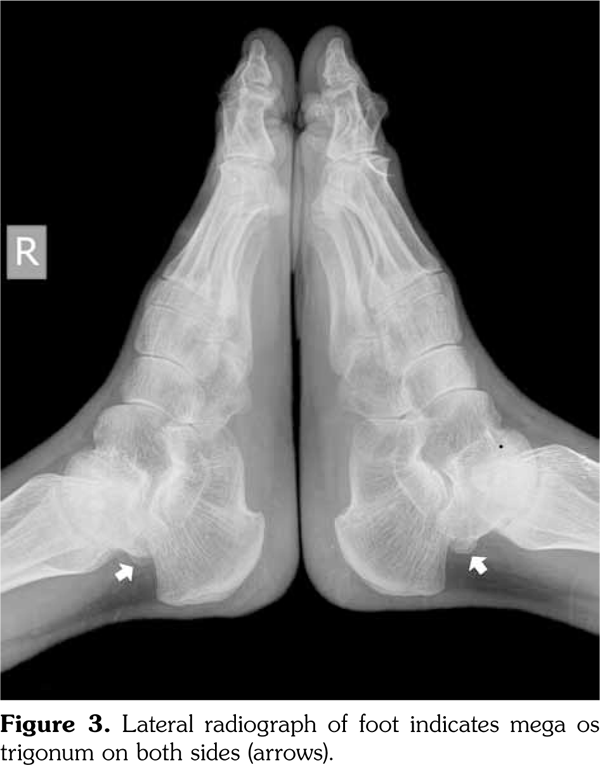

Radiographs of the hands showed enlargement of metaphyses, flattening of epiphyses, and narrowing of joint spaces with no erosions. Lateral radiograph of the foot revealed bilateral large ossified trigonum attached to the talus (mega os trigonum) (Figure 3). Radiographs of the spine showed increased kyphosis, generalized platyspondyly particularly at the thoracolumbar junction, and irregularity of the vertebral end- plates (Figure 4). Magnetic resonance imaging of thoracolumbar spine demonstrated irregularity in vertebral end-plates, multiple disk herniations, and platyspondyly (Figure 5). Dynamic contrast- enhanced magnetic resonance imaging of the wrist did not reveal any signs of synovial inflammation.

Clinical features of PPD have been described in several reports.(9-11) The radiographic features include varying degrees of epiphyseal involvement with enlargement of the epi-metaphyseal region, progressive joint narrowing, generalized platyspondyly, multiple intervertebral herniations, kyphoscoliosis, mega os trigonum and bone destruction with aging.(2,6,10) Our patient had progressive restriction of several joints, IP enlargements, dysplastic bone/cartilage changes, mega os trigonum and platyspondyly, with normal acute phase reactants. The presence of dysmorphic features and the absence of inflammatory signs should alert the physicians for the possible hereditary dysplasias like PPD.